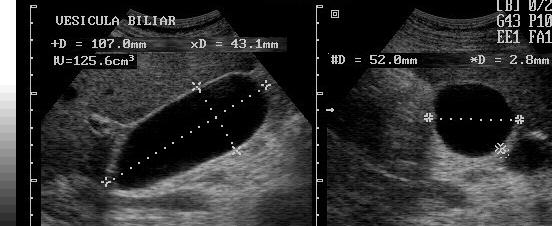

Courvoisier's GB

Distension without wall thickening

due to obstruction distal to the cystic duct

*Panncreatic head mass

* Duodenal papilla mass

*CBD mass

Hydrops GB

Greater than 4cm in diameter